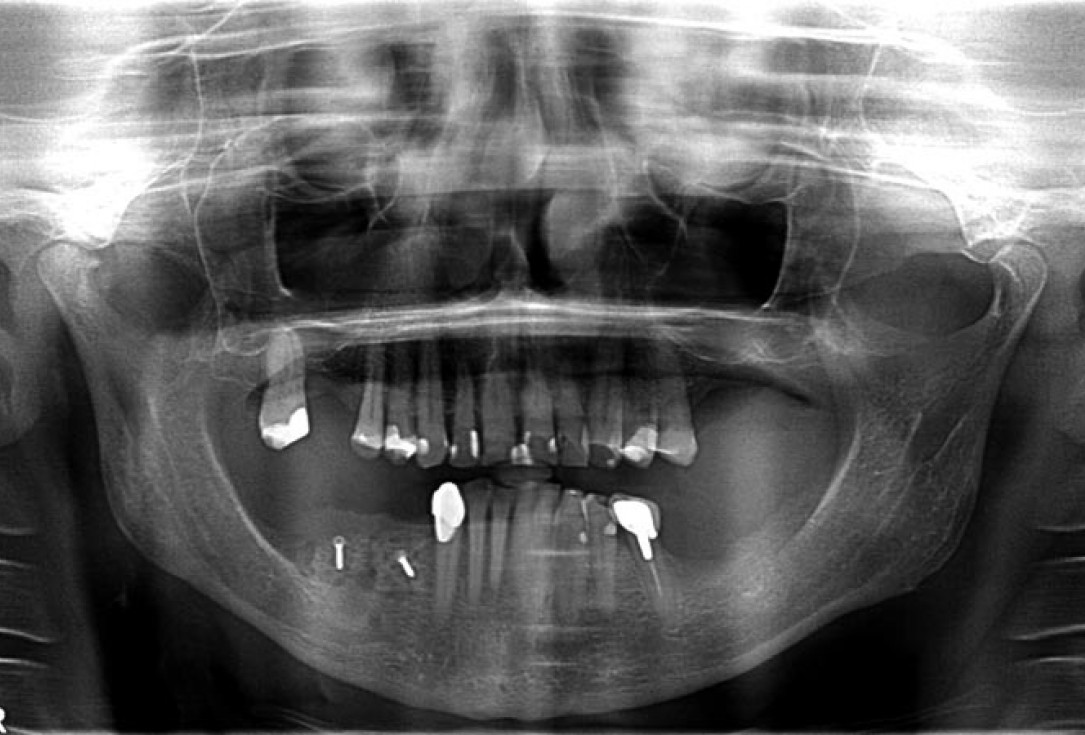

01/14 - Free-end situation in right mandible

02/14 - Preoperative radiological situation